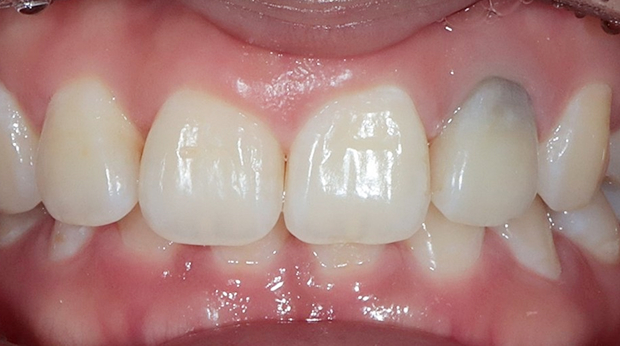

라미네이트